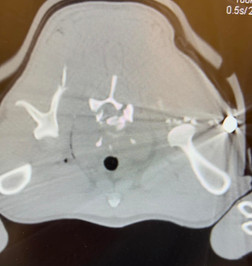

After taking X-rays, veterinarians learned that Nakoa had been shot twice. PAWS of Hawaii said: “To make it worse, this was NOT a BB gun, but real bullets. Someone shot this innocent animal and left him to die on the side of the road.”

Durand also explained that the bullets vets extracted from Nakoa’s body will be sent “over to authorities to try and figure out who did this to this dog.” PAWS of Hawaii said Nakoa was shot with a 9mm.

Furthermore, vets performed a CT scan and as Durand explained: “It's actually very important to do his CT scan because not only will this tell us what's wrong with him, the CT scan would be able to be used in prosecuting whoever it is that did this to him.”